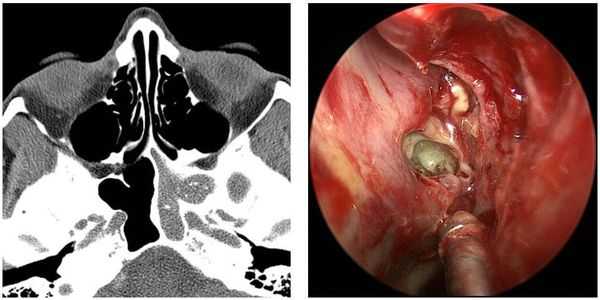

Чтобы определить стадию двустороннего ПРС, нужно исследовать полость носа и пазух с помощью эндоскопии и компьютерной томографии, а также провести морфологический анализ полипозной ткани [13] .

- Эндовидеоскопия — выводит на экран монитора картинку полости носа, которая позволяет увидеть наличие или отсутствие полипов, а также помогает установить стадию болезни. Это исследование выполняет врач-оториноларинголог с помощью специального оборудования — жёсткого или гибкого эндоскопа. Перед началом процедуры пациенту проводят местную анестезию растворами анестетиков в виде спрея или путём введения марлевых турунд в нос. Затем врач очищает полость носа от слизи и поочерёдно заводит эндоскоп на несколько секунд в каждую половину носа. Процедура считается безболезненной, малотравматичной и крайне редко приводит к осложнениям (например, носовому кровотечению, которое легко останавливается).

- Компьютерная томография полости носа и околоносовых пазух (КТ ОПН) — это «послойное» рентгенологическое исследование, которое за счёт малого шага в 1-2 мм между срезами-фотографиями воспроизводит анатомическое строение полости носа и окружающих её пазух. Это позволяет увидеть не только полипы, но и уточнить объём их распространения. По диагностической ценности КТ ОПН более информативна, чем рентгенография.